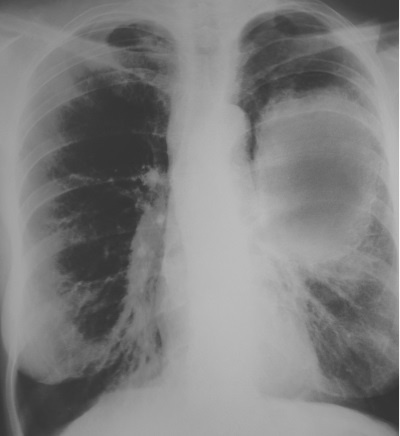

Вдобавок табачный дым содержит ряд токсичных химических веществ, ответственных за развитие рака легких. Чтобы узнать, болен ли пациент раком легких, врачи прибегают к рентгеноскопии. Темные места на рентгеновском снимке показывают участки, где рентгеновские лучи не встретили серьезных преград, тогда как белым цветом отмечены препятствия, например уплотненные ткани или кости.

Позвольте продемонстрировать вам рентгеновский снимок пациента, у которого диагностировали рак левого легкого. Человеку этому было чуть за шестьдесят, и большую часть своей жизни он много курил. Пораженное легкое изобилует рубцовой тканью и раковыми клетками, которые выглядят на снимке как большое белое пятно. Прогноз крайне неблагоприятный. В случаях, когда раковая опухоль легкого превышает в диаметре один дюйм, менее чем пятидесяти процентам пациентов удается прожить пять лет – при том что они получают самые эффективные формы лечения. Этот пациент, скорее всего, умер, не прожив и года.

Иллюстрация к книге — Разорви шаблон! [i_020.jpg]

Как давно вы курите? Испытываете затруднения с дыханием? Вы осознаете, что находитесь на пути к серьезным проблемам со здоровьем? Если вы продолжите курить, очень велика вероятность, что через несколько лет ваши легкие будут выглядеть так же, как на этом снимке. Подумайте, что в таком случае произойдет. Какой эффект это окажет на вашу жизнь и па жизнь ваших близких?

Все это очень плохо. Однако хорошо то, что будущее не предопределено. Плачевной участи можно избежать. Что вы намерены сделать, чтобы в будущем под этим рентгеновским снимком не значилось ваше имя?